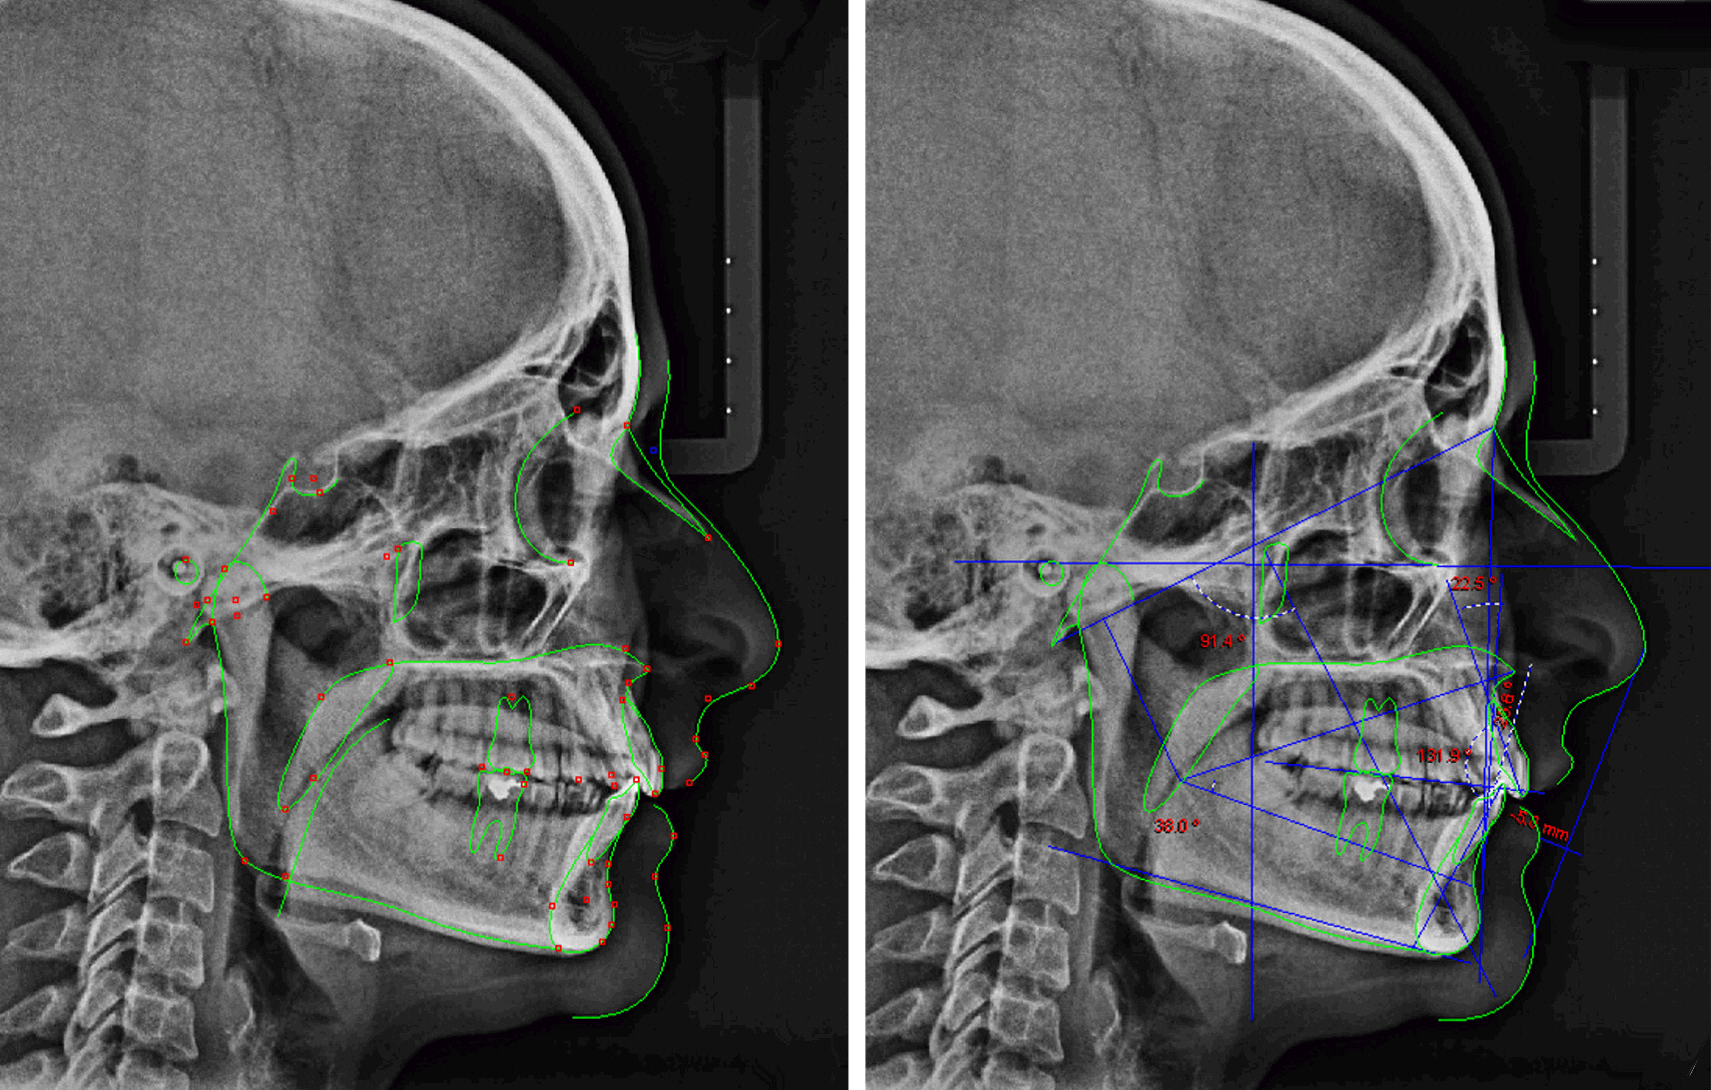

Welcome to ARCUS – Unified Cephalometric Relationship Analysis

At ORTHOPROGRESSIVE, we are proud to introduce ARCUS, an innovative diagnostic tool based on artificial intelligence that transforms cephalometric analysis, offering precise and personalized results for orthodontics.

What is ARCUS?

ARCUS (Unified Cephalometric Relationship Analysis) is an advanced system that uses neural networks and machine learning to process both radiographic images and cephalometric measurements. Its goal is to provide a precise diagnosis of the cranial and mandibular anatomical relationships, now with additional components that include the analysis of parafunctions and growth statistics.

How does ARCUS work?

- Cephalometric pattern classification: Identifying facial and skeletal features that may indicate possible malformations or disorders.

- Diagnosis prediction: Generating reliable diagnoses based on comparisons with large databases, enabling accurate and informed decision-making.

- Orthodontic planning assistance: Providing personalized recommendations for interventions and treatments based on the results obtained.

- Parafunction and growth analysis: Assessing the patient’s habits and growth patterns, offering a long-term perspective on their evolution.

ARCUS is a unified cephalometric diagnostic system designed to analyze craniofacial relationships in an integrated and hierarchical manner, going beyond the isolated interpretation of linear or angular measurements. The core concept of ARCUS is based on the idea that form, function, and growth pattern (Biotype) cannot be evaluated as independent entities, but rather as interrelated units within a dynamic and unified system.